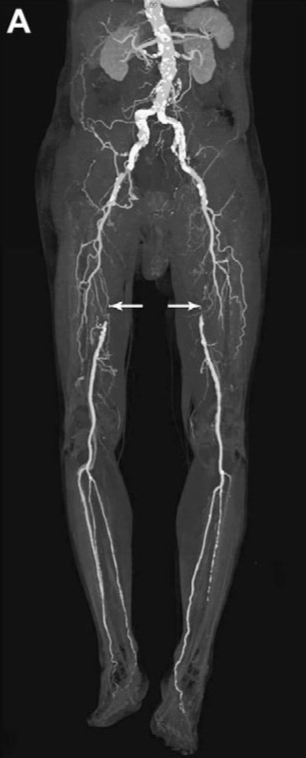

При цьому фахівець отримує об’єктивну інформацію про анатомічну будову судинного русла досліджуваної області, швидкості кровотоку, наявності стенозів (звужень) і оклюзій (повної закупорки), ступеня розвитку колатерального кровообігу в досліджуваній кінцівки.

При виконанні ангіографії фахівець отримує об’єктивну і точну інформацію про будову і ураженні артеріального русла досліджуваної області. Отримані зображення зберігаються в електронному вигляді і згодом можуть бути записані на диск і віддані на руки пацієнту.

Артеріографія нижніх і верхніх кінцівок - при діагностиці облітеруючих захворюваннях артерій (облітеруючий атеросклероз, ендартеріїт).

Це метод візуалізації просвіту артерій та вен шляхом введення в них через катетер рентгеноконтрастних речовин і одночасної рентгеноскопії (відеозапису рентгенівської зйомки), з фіксацією і обробкою отриманого зображення на спеціальному обладнанні.